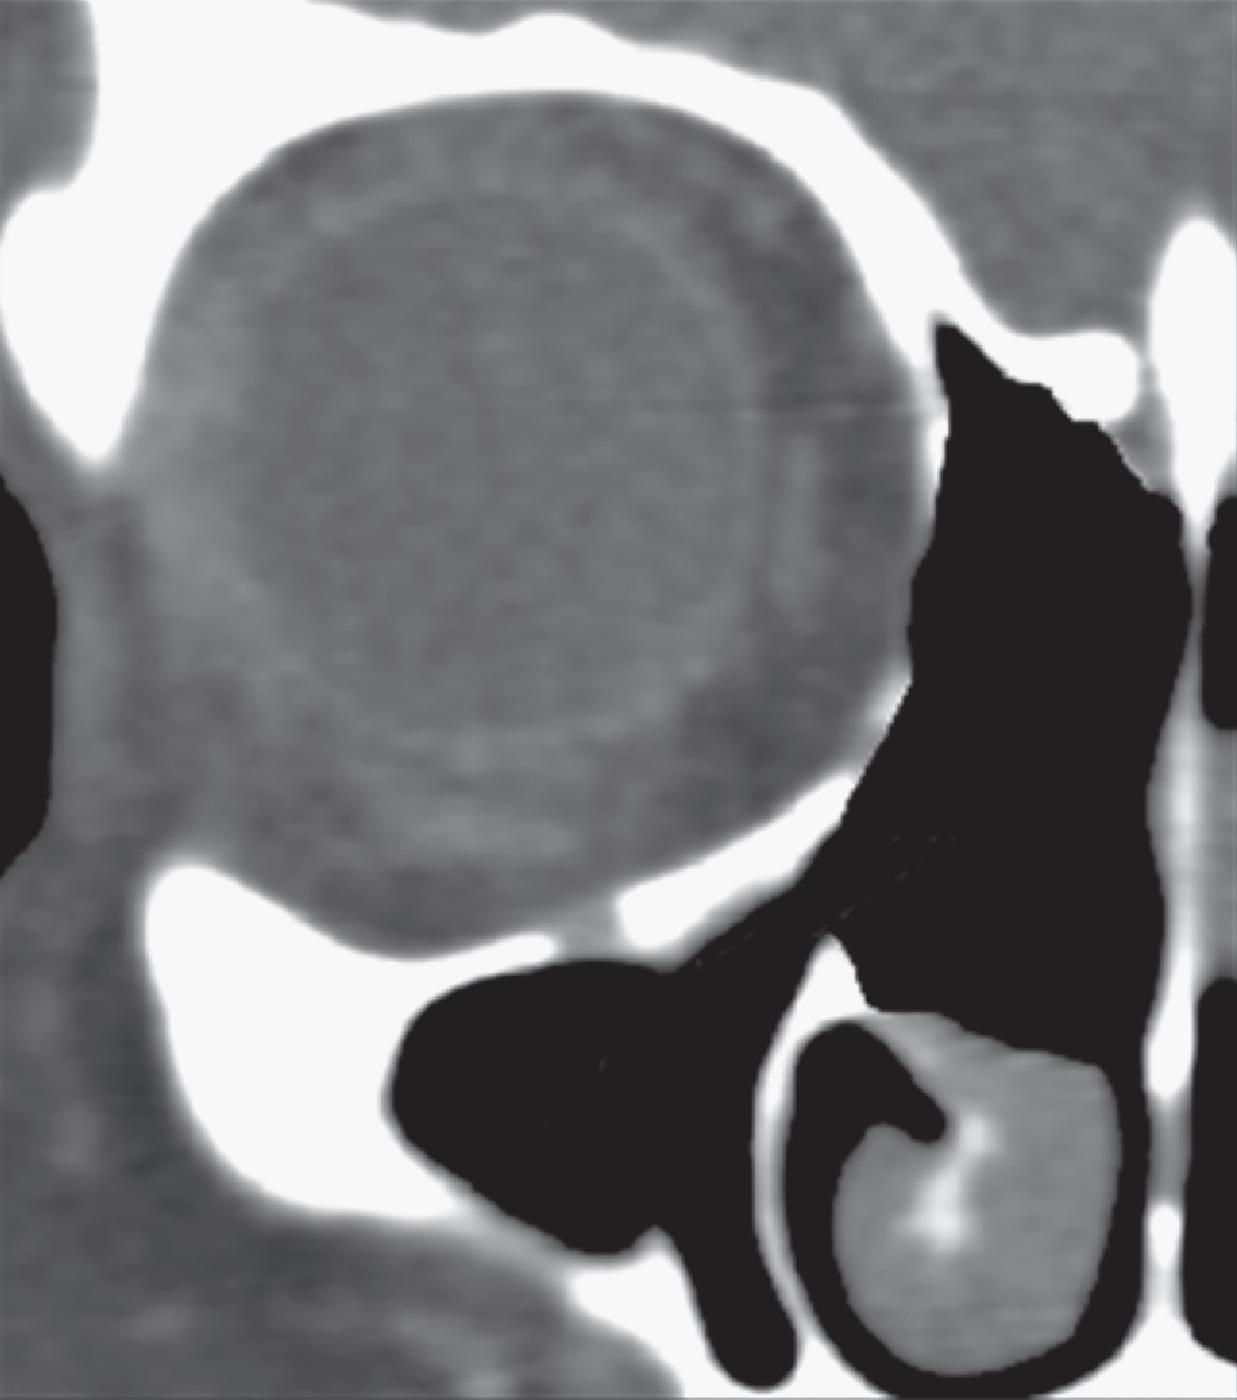

1-16. Relação da bulha etmoidal com a órbita em corte axial, coronal e sagital, respectivamente.

A bulha etmoidal lembra a forma de uma meia-lua e se encaixa na parede medial da órbita (lâmina papirácea) criando, posterossuperiormente (em sua relação com a porção vertical da lamela basal), um recesso algumas vezes chamado de seio lateral e outras de recesso suprabulhar, onde se abrem a própria bulha e cavidades etmoidais vizinhas.

Posterior à bulha etmoidal encontra-se a principal estrutura que fixa a concha média na órbita e na base do crânio: a lamela basal. Esta lamela, como a própria concha média, é oblíqua em relação à lâmina papirácea tanto no sentido anteroposterior como no superoinferior e delimita posteriormente a câmara anterior.